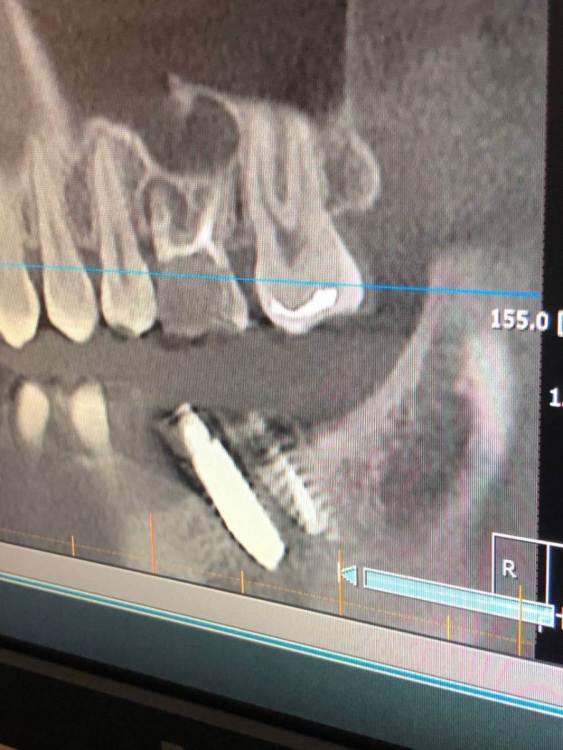

Stoyana Опубликовано 22 мая, 2023 Поделиться Опубликовано 22 мая, 2023 Здравствуйте ! Прошу прокомментировать замену имплантов . 10 лет назад были установлены 2 импланта , 6 на место удаленного зуба , и 7 - в качестве антагониста верхней 7 . Устанавил тот же доктор , по гарантии . Приняли решение заменить импланты , так как коронка с 6 сломалась , на 7 сломался абатмент . После операции , очень болит 5 , ноющая боль , плюс болезненные ощущения при глотании , болит челюсть в области операции . Доктор утверждает что по снимку проблем нет . Прошу прокомментировать ситуацию . Первые 2 фото - импланты которые заменили . 3 и 4 фото - новые импланты Ссылка на комментарий